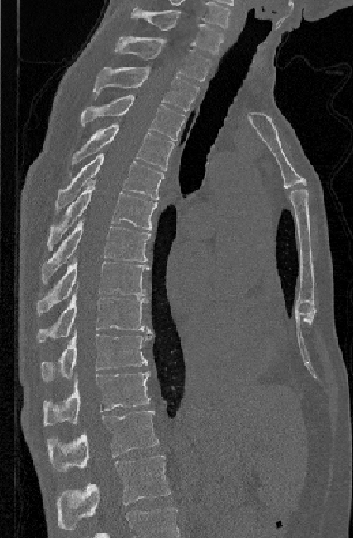

Vertebrae localization, segmentation and identification in CT images is key to numerous clinical applications. While deep learning strategies have brought to this field significant improvements over recent years, transitional and pathological vertebrae are still plaguing most existing approaches as a consequence of their poor representation in training datasets. Alternatively, proposed non-learning based methods take benefit of prior knowledge to handle such particular cases. In this work we propose to combine both strategies. To this purpose we introduce an iterative cycle in which individual vertebrae are recursively localized, segmented and identified using deep-networks, while anatomic consistency is enforced using statistical priors. In this strategy, the transitional vertebrae identification is handled by encoding their configurations in a graphical model that aggregates local deep-network predictions into an anatomically consistent final result. Our approach achieves state-of-the-art results on the VerSe20 challenge benchmark, and outperforms all methods on transitional vertebrae as well as the generalization to the VerSe19 challenge benchmark. Furthermore, our method can detect and report inconsistent spine regions that do not satisfy the anatomic consistency priors. Our code and model are openly available for research purposes.